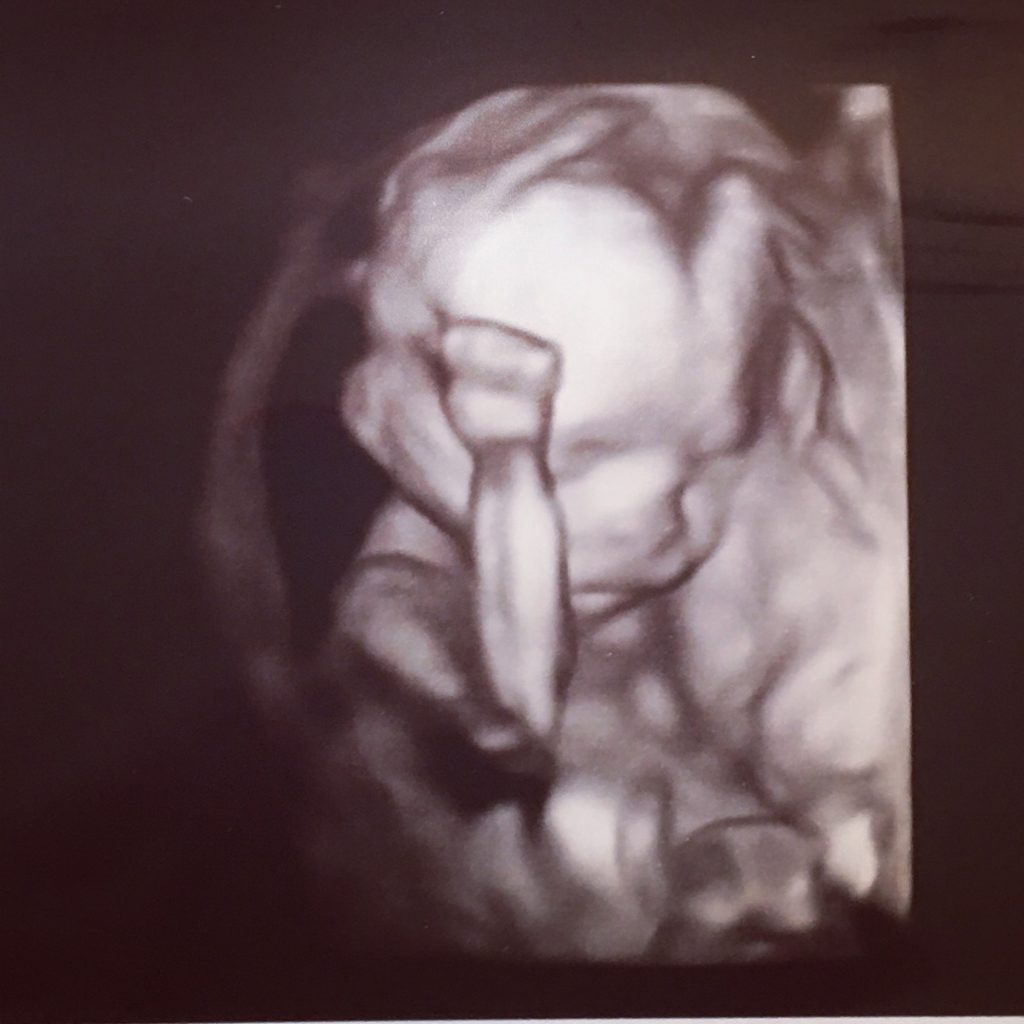

That was, until now. We are now half way through the process of growing this baby girl. She is officially half cooked. We got another glimpse at her on Saturday and she is a little swoon worthy . She is sweet and considerately small and spent most of the scan hiding her head away from the light and clutching her fists to her temples, as if vexed by a great injustice she wasn’t quite sure how to right.